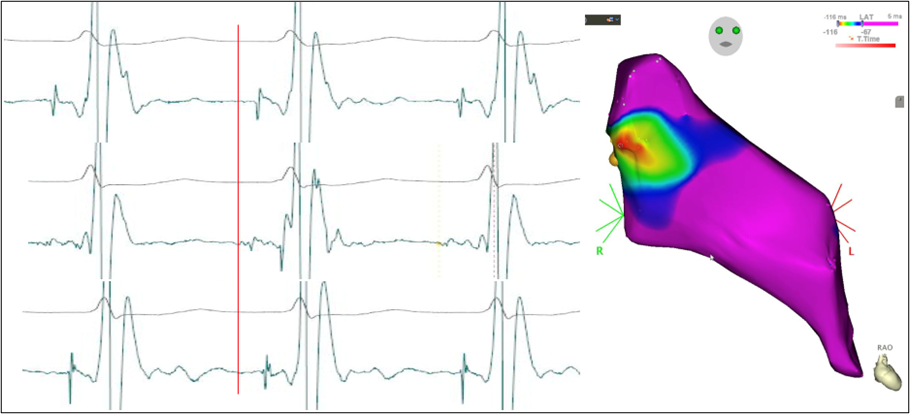

Nach komplikationsloser transseptaler Punktion erfolgt daraufhin die Erstellung eines Aktivierungsmaps des basalen Septums. Anschließend erfolgt die Markierung der His-Region. Im Bereich der frühesten Aktivierung zeigt sich das Intervall von Purkinje Potential zu QRS-onset gleich lang wie in der Tachykardie, sowie ein perfektes Entrainment (Abbildung 5 und 6).

EP-Fall_7_24_5

Abbildung 5: Aktivierungsmap des basalen Septums sowie entsprechende intrakardiale Signale während des Mappings.